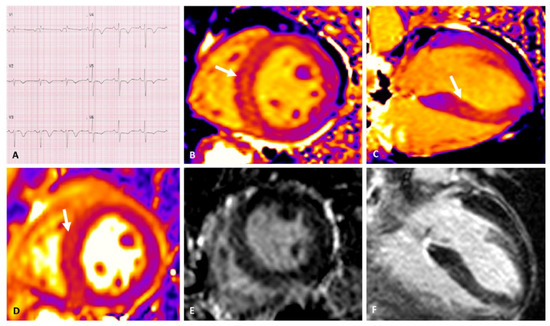

- Camastra, G.; Arcari, L.; Ciolina, F.; Danti, M.; Cacciotti, L. Cardiac magnetic resonance imaging of transient myocardial dysfunction in a patient treated with checkpoint-targeted immunotherapy. Eur. J. Cancer 2020, 144, 389–391. [Google Scholar] [CrossRef]

- Arcari, L.; Camastra, G.; Ciolina, F.; Danti, M.; Cacciotti, L. Imaging Edema in Immune Checkpoint Inhibitor Myocarditis: A Moving Target. J. Am. Coll. Cardiol. 2021, 78, 416–417. [Google Scholar] [CrossRef]

- Ida, M.; Nakamori, S.; Ishida, M.; Dohi, K. Management of immune checkpoint inhibitor myocarditis: A serial cardiovascular magnetic resonance T2 mapping approach. Eur. Heart J. 2021, 42, 2869. [Google Scholar] [CrossRef] [PubMed]

- Sato, T.; Nakamori, S.; Watanabe, S.; Nishikawa, K.; Inoue, T.; Imanaka-Yoshida, K.; Ishida, M.; Sakuma, H.; Ito, M.; Dohi, K. Monitoring of the Evolution of Immune Checkpoint Inhibitor Myocarditis with Cardiovascular Magnetic Resonance. Circ. Cardiovasc. Imaging 2020, 13, 10633. [Google Scholar] [CrossRef] [PubMed]